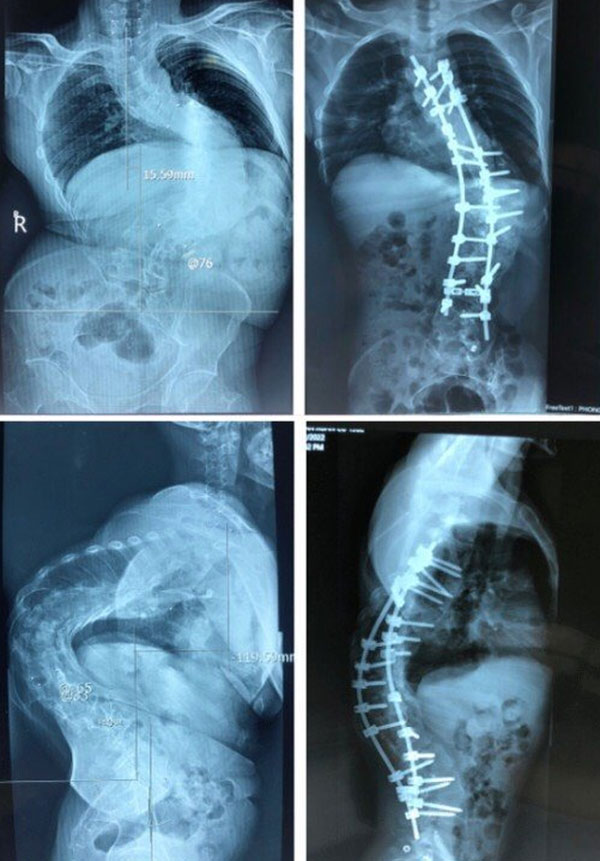

27/12/2022 20:58Cắt xương sườn, vén phổi chữa bệnh 'siêu gù' cho người đàn ông mang 'mai rùa' hàng chục năm

Theo VietNamNet, anh N.V.A (40 tuổi, Nghệ An) mắc bệnh gù vẹo cột sống nhưng vì kinh tế khó khăn, anh chấp nhận sống với hình thể biến dạng suốt hàng chục năm qua.

Gần đây, mức độ gù vẹo ngày càng tăng lên, kèm theo đau cột sống, khó thở do biến dạng cột sống nên anh và gia đình tìm đến một số bệnh viện điều trị. Tuy nhiên, anh chưa thể thực hiện phẫu thuật.

Tại Khoa Chấn thương Chỉnh hình cột sống, Bệnh viện Trung ương Quân đội 108 (Hà Nội), qua hình ảnh X-quang, tình trạng thực tế của bệnh nhân, các bác sĩ xác định đây là một ca bệnh đặc biệt khó, góc vẹo rất lớn T6L3 khoảng 126 độ. Hơn nữa, ca bệnh này càng khó khăn hơn do kèm theo gù cũng rất lớn, trên 100 độ.

Trao đổi với Sức Khỏe & Đời Sống, TS.BS Phan Trọng Hậu – Chủ nhiệm khoa Chấn thương Chỉnh hình cột sống, BV Trung ương Quân đội 108, cho biết trước đây, các bác sĩ cũng đã tiến hành phẫu thuật cho nhiều bệnh nhân vẹo lớn nhưng hầu hết là vẹo đơn thuần, không kèm theo gù, và chủ yếu là các bệnh nhân trẻ tuổi, cột sống khá mềm dẻo.

Trường hợp này phức tạp hơn, qua nghiên cứu y văn và bằng những kinh nghiệm trước đây, các bác sĩ đã quyết tâm phẫu thuật trả lại vóc dáng cho bệnh nhân. Bệnh nhân trải qua 2 thì mổ:

Thì thứ nhất, đi lối trước, cắt xương sườn, vén phổi, cắt tối đa được 4 đĩa đệm để làm lỏng cột sống, sau đó lắp khung Halo kéo dãn trên giường nghiêng 30 độ, trong thời gian 3 tuần, với cân nặng tăng dần đến lúc đạt mức tối đa là 50% cân nặng của bệnh nhân.

Cũng bởi vì ca bệnh gù rất lớn nên các bác sĩ đã quyết định cắt V xương ở 3 mức để nắn chỉnh. Để thực hiện điều này phải là cả một sự quyết tâm lớn, bởi vì thời gian mổ dài, kỹ thuật khó, nhiều nguy cơ tai biến biến chứng. Cuộc đại phẫu cân não kéo dài nhiều tiếng.

Sau mổ, hình thể người bệnh đã gần như bình thường, chiều cao tăng thêm vài cm, bệnh nhân A. đã cảm thấy thở dễ hơn, đi lại cũng ổn hơn, và quan trọng nhất là đã tự tin hơn rất nhiều trong cuộc sống.

Sau hơn một tháng, bệnh nhân đã phục hồi rất tốt. Chỉ còn một thời gian ngắn nữa, anh sẽ được trở về đoàn tụ với gia đình. Chuyến này về quê, chắc hẳn anh sẽ nhận được sự ngạc nhiên, bất ngờ, những lời chúc mừng của họ hàng, người thân, bạn bè trước thay đổi ngoạn mục về ngoại hình, thông tin trên Dân Trí.